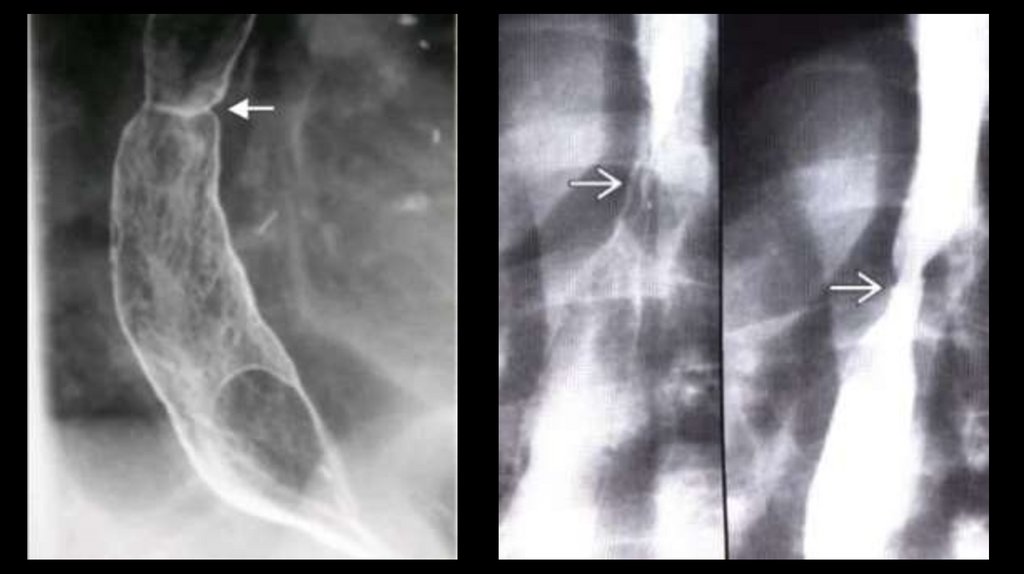

• Дивертикул Ценкера - протрузия

• Рентгенологическая

картина:

заполненное

контрастом

мешковидное выпячивание задней

стенки шейного сегмента пищевода

(С5-С6).